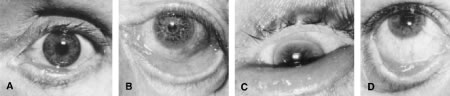

Ectropion is an eversion of the eyelid away from the globe. It is classified according to its anatomic features as involutional, cicatricial, tarsal, congenital, or paralytic (Fig. 2). Surgical approaches can be directed toward the underlying etiologic factors.

Fig. 2. Clinical presentation of ectropion. A. Medial ectropion. B. Generalized ectropion with retraction of eyelid. C. Tarsal ectropion, with total eversion of tarsus. D. Cicatricial ectropion developing following orbital floor exploration.